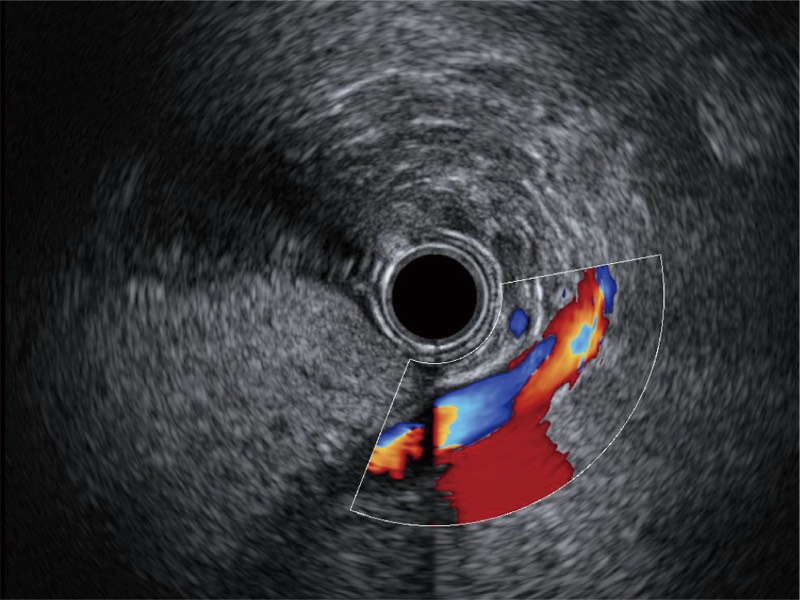

清晰顯示膽總管及周?chē)芊植?/p>

肝左葉和肝靜脈的橫截面